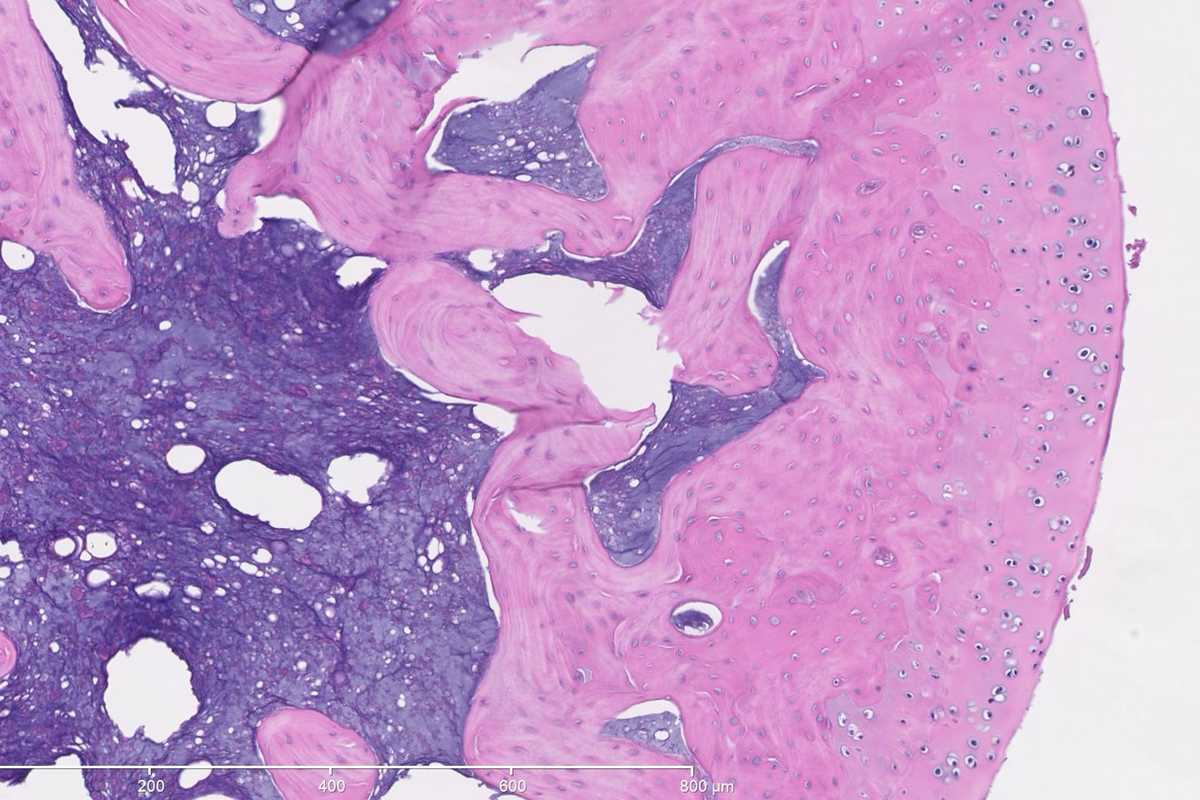

“We get high-resolution images of tissue histology and also acquire magnetic resonance images,” Lake said. “These are rich sources of data that provide a lot of insight, but there are also likely additional patterns that we’re not seeing currently. We're developing machine learning algorithms to try to detect these patterns and extract more information from these images than we can visually, then link the data modalities together.”

Lake’s ultimate goal is to detect how different tissues are changing following injuries and treatments so that they can determine which therapeutic parameters are most critical to optimize tissue healing and functional recovery.

“We want to determine whether the treatments are effective and improving tissue-level properties or whether the tissues are still injured,” Lake said. “Ideally, if we could correlate the data from the MRI, which is noninvasive, with the data we're getting from more invasive tissue-analysis techniques, that would lend better towards translation to humans.”